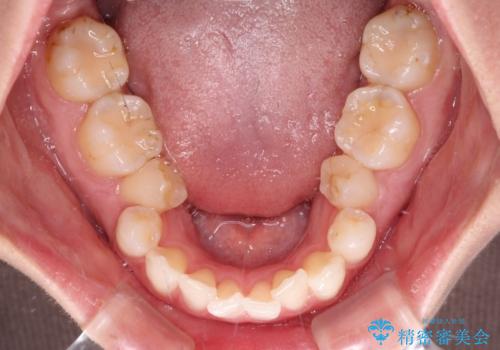

- 上下前歯のデコボコ、特に右上の八重歯を気にして来院された患者様です。

妊娠、出産の予定があり、毎月の通院が困難となる可能性があったため、インビザラインによる矯正治療を行うこととしました。

事前に親知らずを抜歯しておき、出産時期に困ることのないように準備をした上で治療を開始しました。